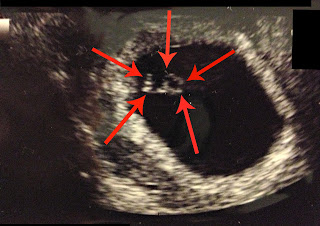

Then we headed to get blood work, and after that the hospital for my ultra sound. I've never had an ultra sound so that was an experience all on it's own. For the most part the technician was looking at my uterus and organs and whatnot, nothing too interesting. Chris was absolutely enthralled which made her laugh because she wasn't looking at anything.

But then she turned the screen so I could see, and what I saw was the cutest little blob I have ever seen and a flickering spec that turned out to be the heartbeat.

| There is it! My cute little blob! |

Okay, I know there isn't much to look at, but to me it's incredible! That little blob is actually a growing baby, in my belly!!!